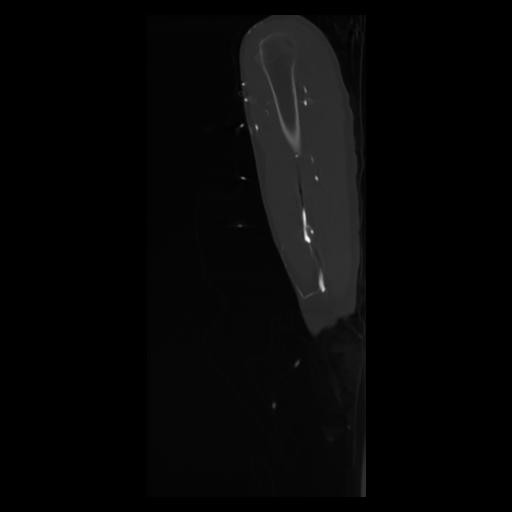

30 CUERPO,CE,Sagittal,3.000,CUERPO,Sagittal,